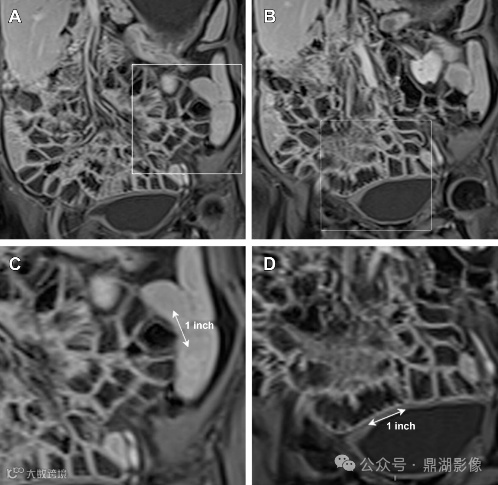

图3.磁共振小肠造影对肠皱襞模式的评估。(A, B)静脉注射对比剂增强MRI小肠造影 T1WI脂肪抑制冠状位图像显示空肠(A)肠皱襞数量减少,回肠(B)肠皱襞数量增加。(C, D)空肠(C)和回肠(D)的放大图像更清晰地显示了肠皱襞模式的反转。双箭头表示每英寸的肠皱襞数量。

在CT和MR小肠造影图像上观察到每英寸(=2.54cm)肠段的皱襞少于或等于3个,则认为空肠皱襞密度降低。在重度乳糜泻中,空肠皱襞可能完全消失。在慢性炎症的情况下,回肠皱襞密度可能代偿性增加,定义为每英寸超过5个皱襞,以增加小肠表面积。皱襞数量的增加代表回肠对空肠吸收能力下降的一种适应。

空回肠皱襞模式反转(称为回肠空肠化,空肠皱襞减少,回肠皱襞增加)是乳糜泻最特异的征象,文献报道其敏感性和特异性(阳性预测值和阴性预测值)接近100% 。 5cm距离内回肠皱襞数量多于空肠皱襞数量时,则被认为是阳性。